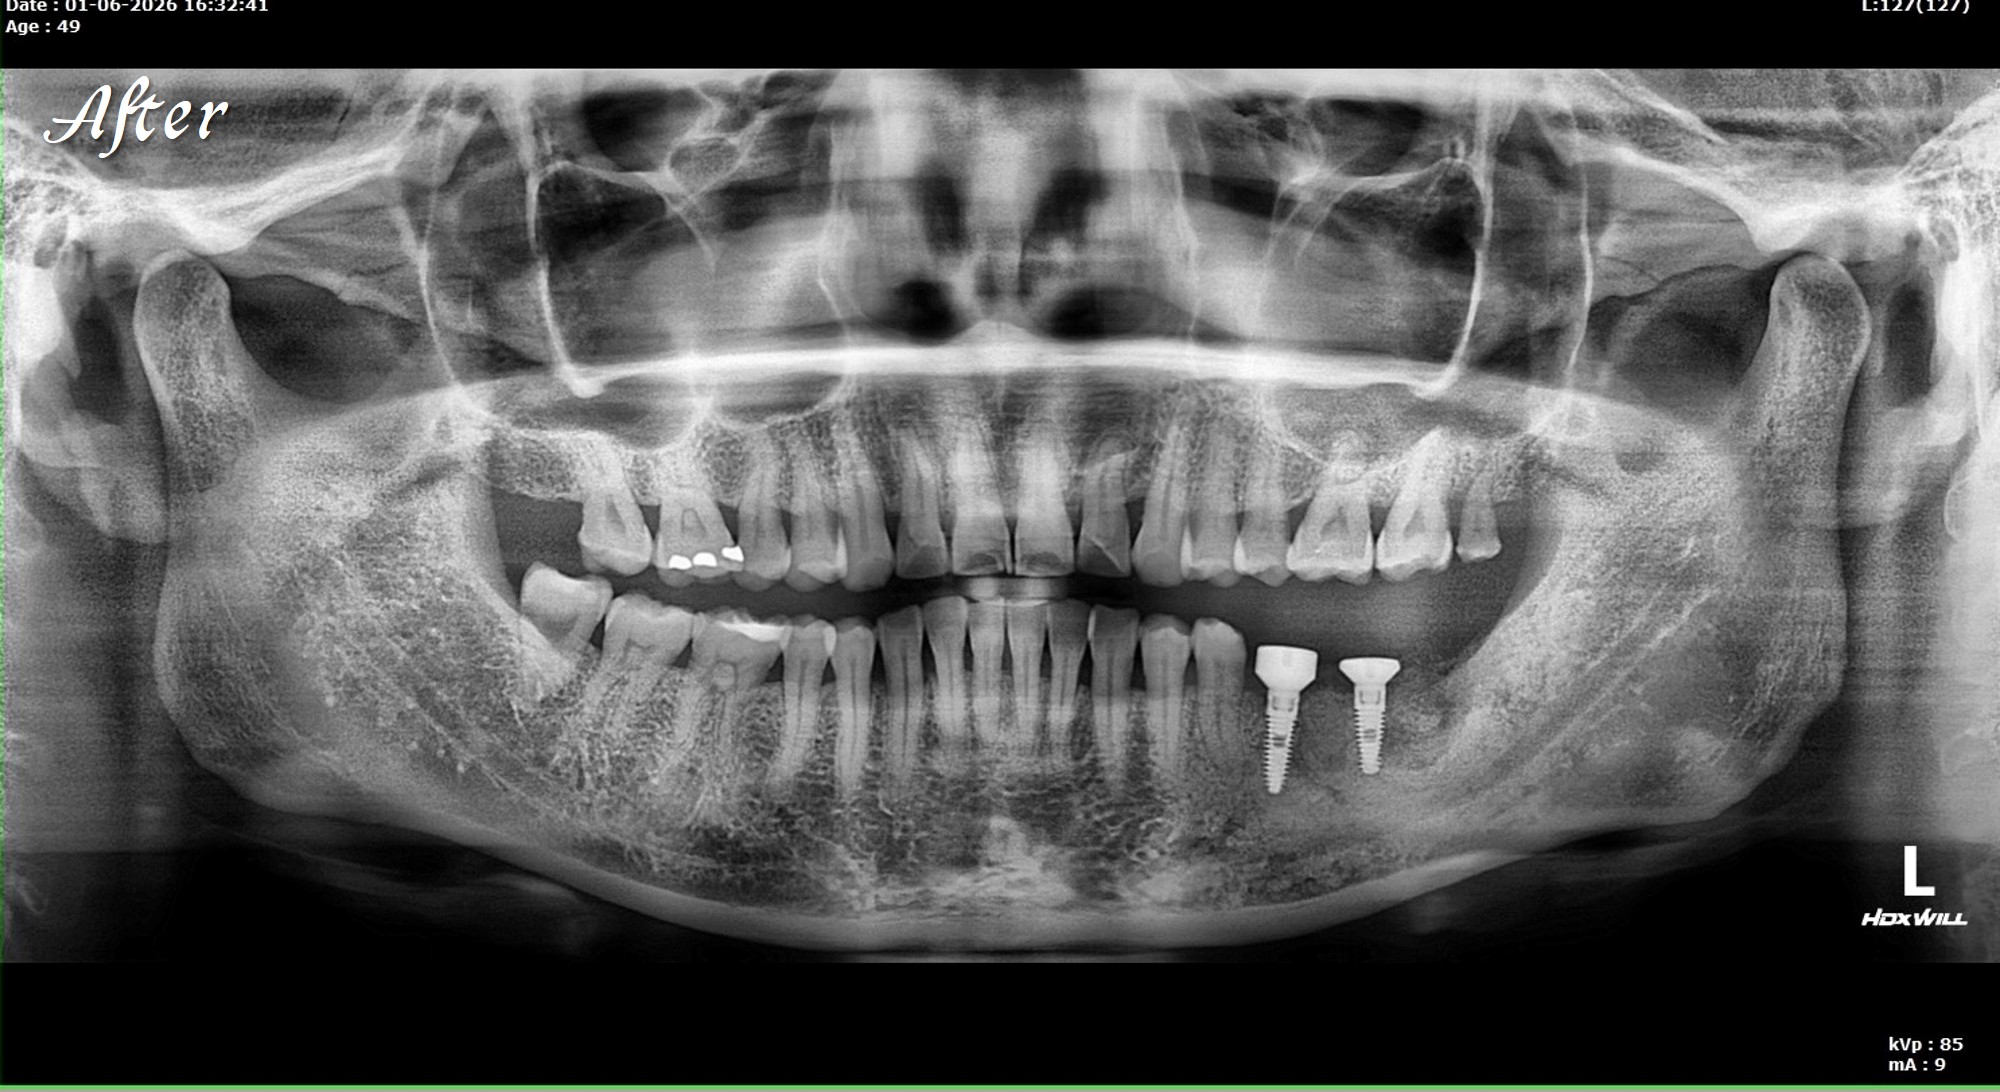

精奈創一鑽植牙系統團隊|3.5個月完成的植牙案例

一位初診新患者,陳博士評估後進行治療。

植牙後約3.5個月骨整合完成,骨頭穩定生長良好。